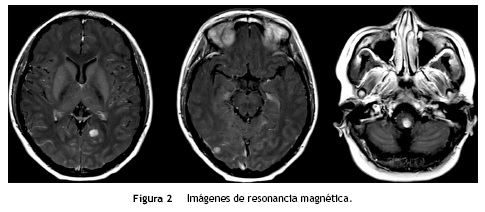

A continuación se presenta una serie de imágenes en las que se compara la calidad de la imagen en la TAC de simulación con la resonancia magnética. Posteriormente, se presentan las imágenes de la fusión realizada y los volúmenes de delimitación. Por último, se muestran las imágenes de dosimetría en las cuales es posible apreciar la diferencia de dosis administrada a las lesiones y a los órganos sanos a riesgo.

En la figura 2 se presentan imágenes de RM en los mismos cortes que la figura 1. Las imágenes de RM utilizadas fueron obtenidas de estudios realizados al paciente previamente al ingreso en nuestra institución. Se observa que los volúmenes de tratamiento (lesiones metastásicas) son claramente observables en cuanto a su localización y tamano. Asimismo, las áreas hipocampales son de mejor definición en comparación con las imágenes de TAC.